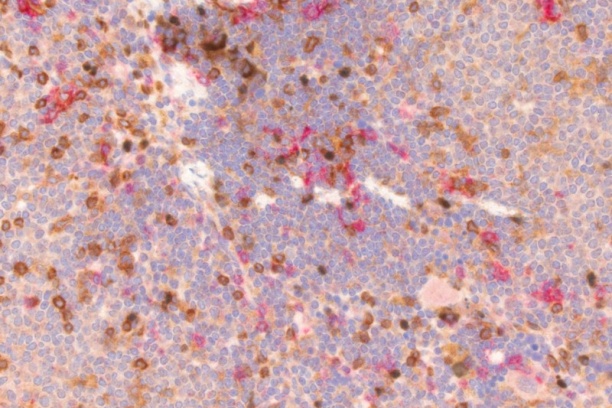

- Research histology including, immunohistochemistry and novel antibody development

- Comprehensive, state of the art diagnostic, necropsy and comparative pathology services for animal model systems with specific expertise and focus on mouse models